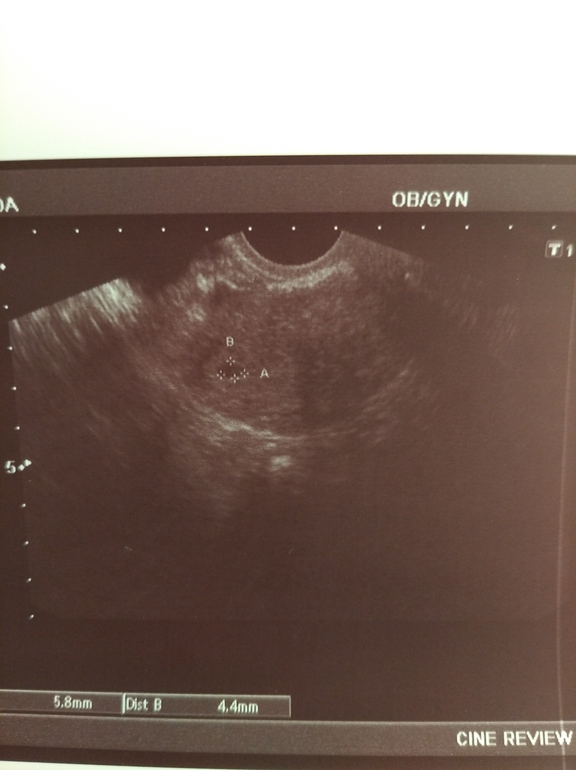

И тут такое! Сегодня мою крошку нашли на УЗИ!!! Я так счастлива

12 дпо 97

14 ДПО 422

Сегодня день х, как узист увидел и нашел я не знаю, но это такое чудо!